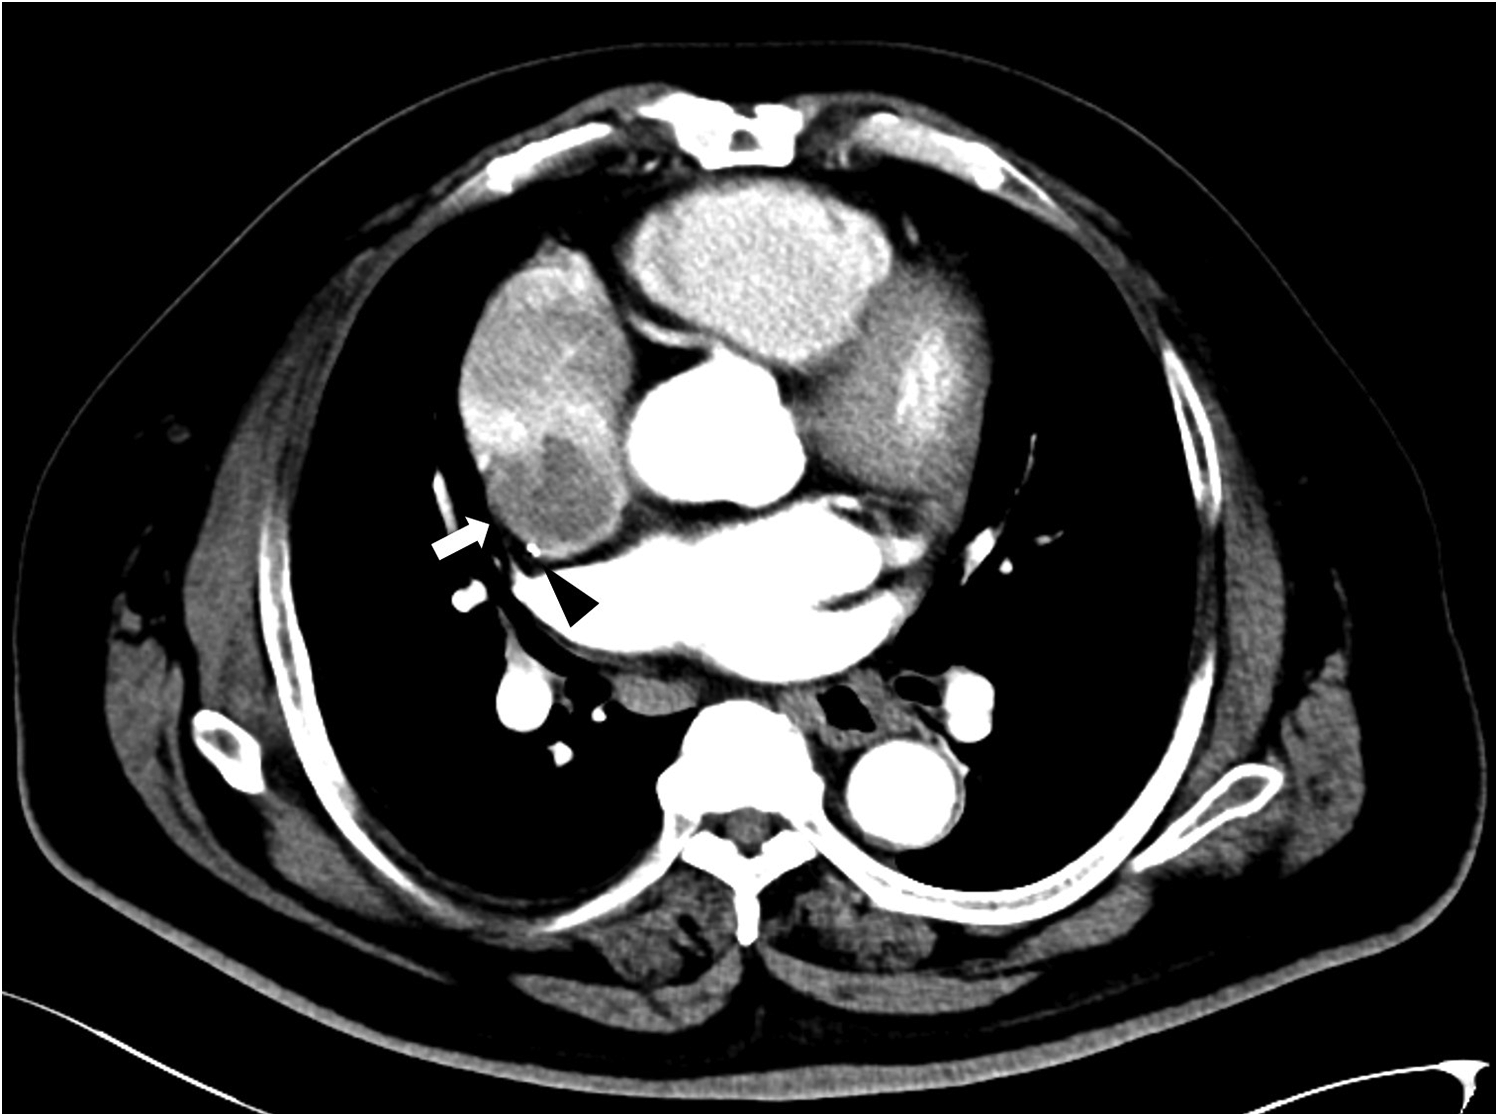

A 58-year-old male with a medical history of hypertension, diabetes and gastro-oesophageal junction low-differentiated invasive adenocarcinoma. Preoperative transthoracic echocardiography revealed a mild degree of heart chambers with a 2 mm PFO and valvular function was normal. Electrocardiogram demonstrated AF and ventricular premature beats. On October 26, 2021, a TIVAP was implanted in the patient's right chest wall for chemotherapy, with the tip positioned at the junction of the superior vena cava (SVC) and the right atrium under fluoroscopy. The patient received six cycles of systemic chemotherapy, comprising intravenous oxaliplatin 100 mg/m2 on day 1, oral S-1 80 mg twice daily for 14 days every three weeks. Although the patient has completed the last intravenous chemotherapy in July 2022, the TIVAP was not removed for concern about recurrence. Regular TIVAP maintenance was performed through noncoring needle with 0.9% sodium chloride every four weeks, and the tumor showed complete remission during follow-up. On February 11, 2024, the patient presented to the emergency department with dizziness and left limb weakness lasting two days. Physical examination revealed left nasolabial fold flattening, rightward deviation of the jaw upon mouth opening, and inaccuracy in the left finger nose test. Cranial CT indicated a right temporal lobe infarction (Figure 1). Symptoms improved following the treatment of clopidogrel 75 mg and atorvastatin 20 mg daily. Ultrasound examination showed no abnormalities in the carotid and vertebral arteries, and no thrombosis in the deep and superficial veins of the lower limbs. Transesophageal echocardiography revealed a 44 mm × 23 mm mass in the right atrium and a 2 mm PFO. Further cardiac CT confirmed the mass at the entrance of the SVC into the right atrium, with normal left heart and pulmonary arteries (Figure 2). Differential diagnosis included atrial myxoma, thrombosis, metastatic tumors and infective endocarditis-related vegetations. Two weeks after anticoagulation with vitamin K antagonists, the mass remained static. The TIVAP was used for administering therapy for normal function during this stage. On March 21, 2024, the patient underwent right heart mass resection, PFO repair, TIVAP removal and left atrial appendectomy for reducing the risk of thrombosis in the future. Postoperative pathology showed fibrous tissue without proliferative cells, revealed that the mass was thrombosis (Figure 3). The patient recovered well and was discharged, with no embolic events during follow-up on continuous rivaroxaban 20 mg daily.

Figure 2

Cardiac CT showed a mass connected to the lateral-posterior wall of the right atrium (white arrow), and the catheter was located behind the mass (black triangle).